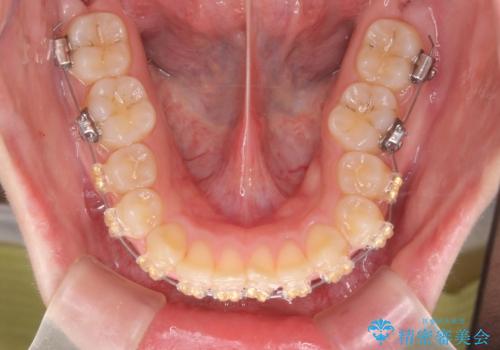

深い噛み合わせ、すきっ歯の改善 ワイヤーを用いたマルチブラケット矯正

- 矯正装置

- ワイヤー矯正

- 噛み合わせが深く、前歯が突き出て隙間が出てきたことの改善を希望され矯正治療の相談で当院に初診来院されました。

ワイヤーを用いたマルチブラケット矯正を行うことで深い噛み合わせを改善し、前歯の隙間もなくし審美的な歯列へと治療をおこなっていきます。